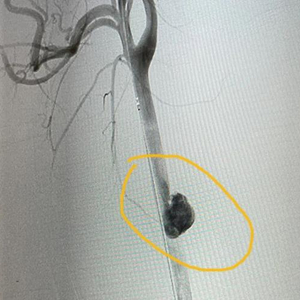

根据陈先生的病史和术前CT影像,赵文军手术团队迅速制定好了手术方案。“分两步走,先用支架从里面堵住血管破损处,再从颈部开刀进去修补血管。”

使用的支架,全称是人工血管覆膜支架,从大腿根部处通过穿刺血管置入,送到颈动脉破损处。这是介入手术范畴,需要医学影像引导,杂交手术室为患者节约救命时间的优势这时就显现出来了。

当支架在陈先生颈部顺利打开,相当于给颈动脉穿了一件“内甲”,完美堵住了出血口。

“外围血肿清除后,能看到长约1厘米的颈动脉破口,还能看到里面的人工血管覆膜支架。”赵文军说,手术视野清晰,能让外科医生更快速地完成缝合。